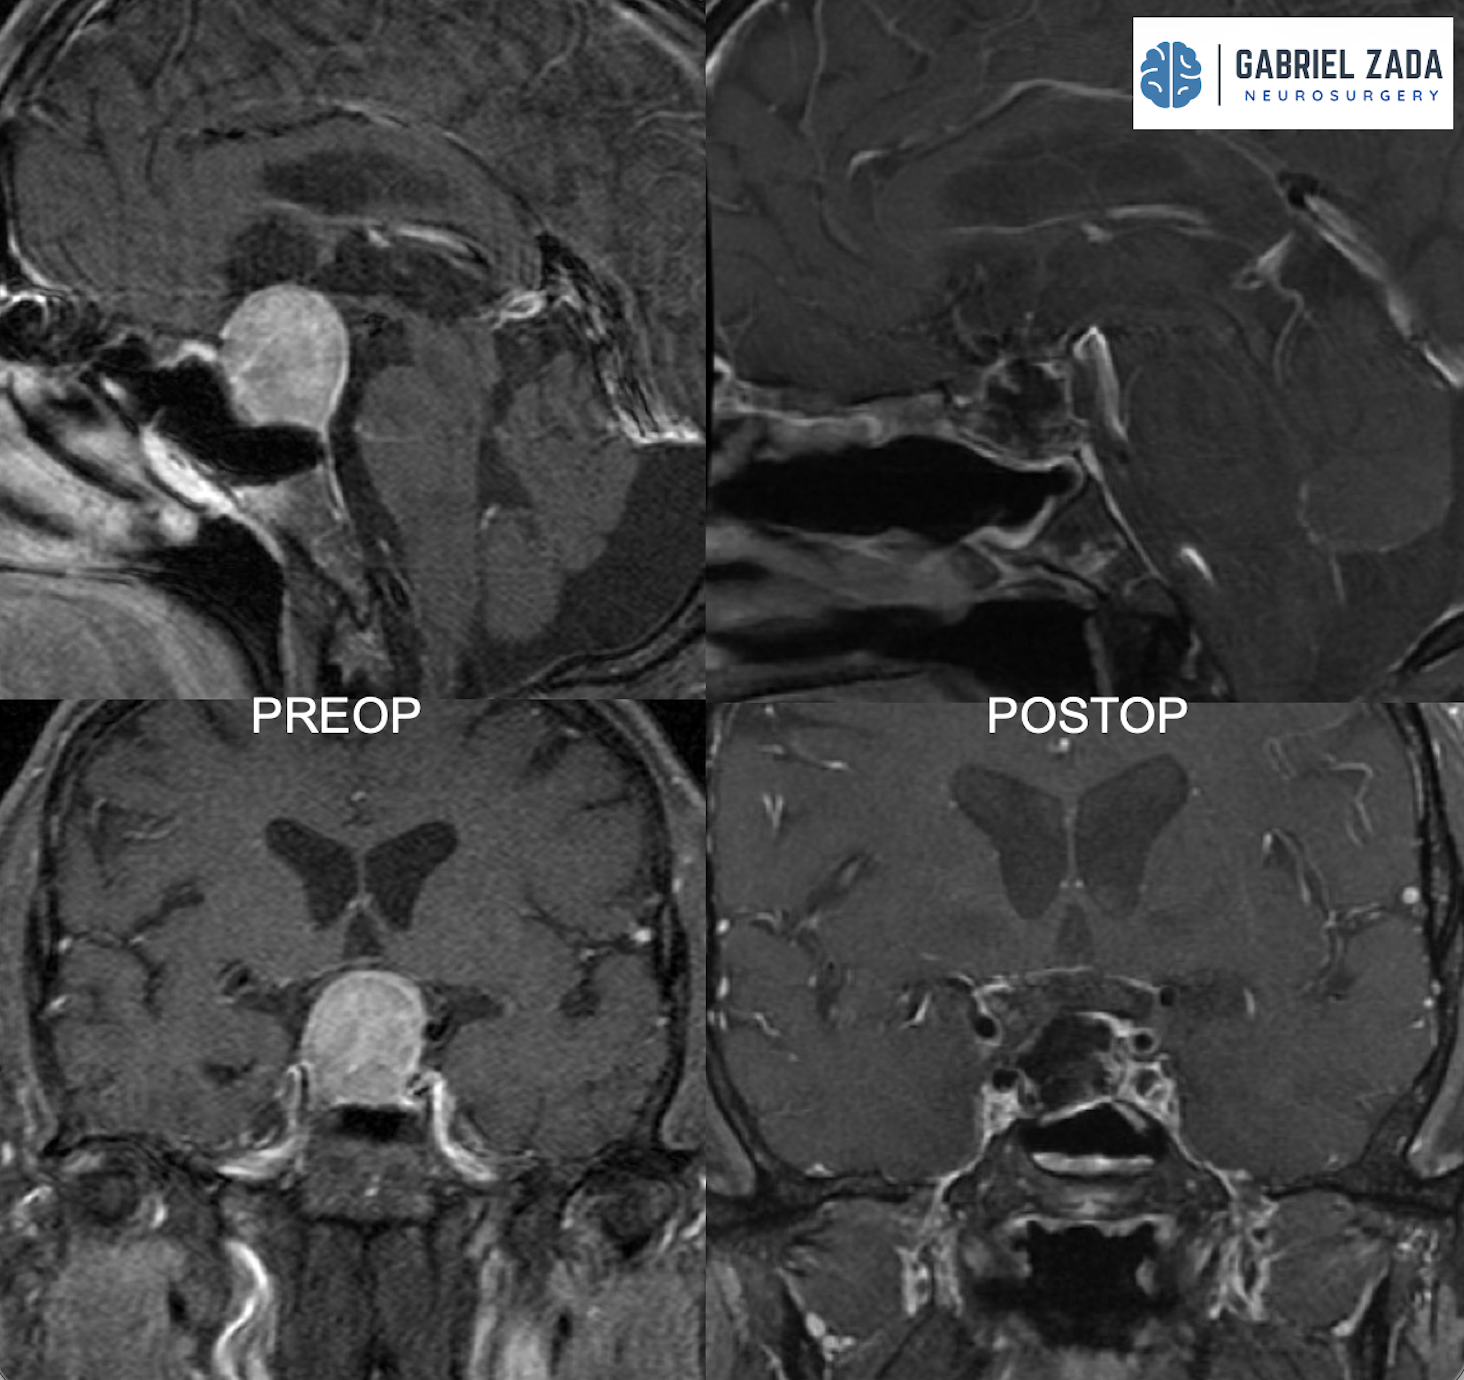

Craniopharyngioma treatment

• Complex tumors near the pituitary gland that require specialized neurosurgical expertise.